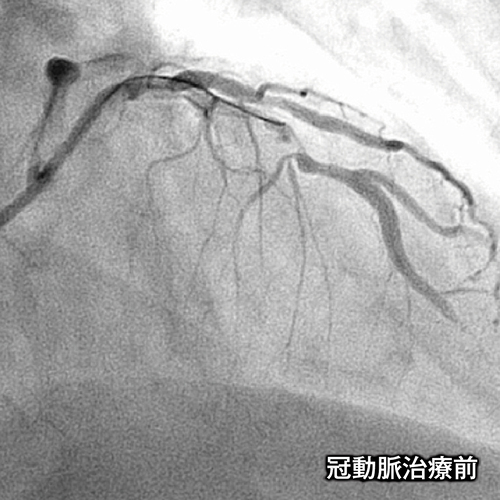

冠動脈治療前の画像

当院では、カテーテルから造影剤を注入し、冠動脈を直接造影する検査(CAG)や、カテーテルを用いて動脈硬化で狭くなった冠動脈を拡張させる経皮的冠動脈形成術(PTCAまたはPCI)などを行っています。